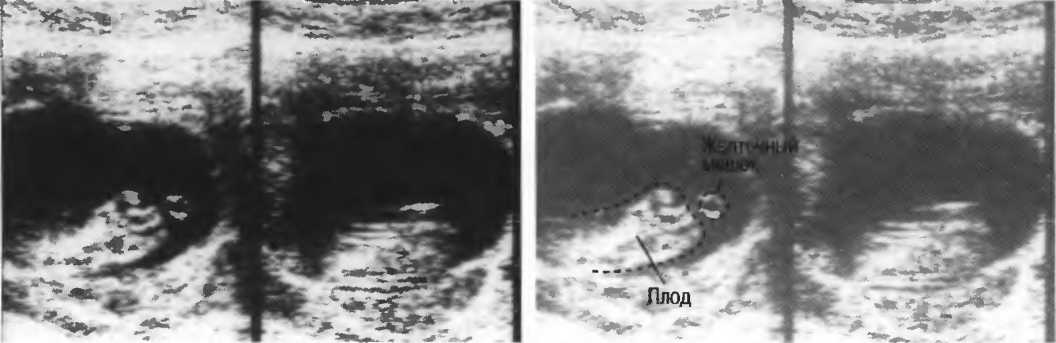

Рис. 12. Фокусировка правильна слева, так как визуализируются детали желточного мешка. Справа детали не видны, так как фокусное расстояние значительно больше.

На эхограммах рис. 13 представлены различные варианты регулировки чувствительности и усиления по глубине.

Рис. 13а. Эхография печени. Слева: слишком слабое усиление глубоких отделов. Справа: слишком слабое усиление поверхностных отделов.

Рис.13б. Эхография печени. Слева: общее повышение чувствительности. Справа: общее понижение чувствительности.

Рис.13в. Эхография печени. Слева: слабое усиление срединных отделов печени, справа: правильная регулировка, усиление по глубине.

Рис. 13г. Головка плода. Слева: общая чувствительность слишком высока. Справа: общая чувствительность определена правильно, однако она слишком высока для точного измерения бипариетального диаметра.

Рис. 13д. Общая чувствительность слишком низка для исследования внутренней зхоструктуры, но достаточна для точного измерения бипариетального диаметра.

Рис.13е. Слева: плохая визуализация в результате слишком высокого усиления передних отделов; сравните нечеткое изображение передней части головки с достаточно четким изображением задних отделов (сравните рис. 13ги 13д;. Справа: регулировка по глубине была изменена; теперь определяется слишком низкое усиление близких структур и слишком высокое усиление глубокорасположенных структур.